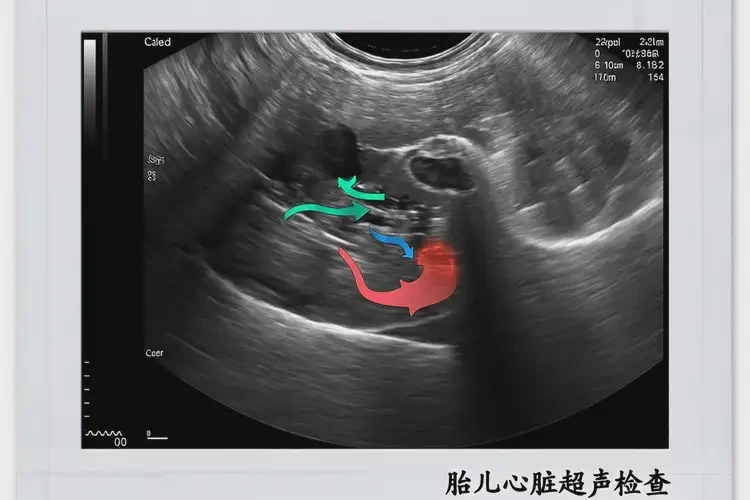

懷孕第10周胎心90寶寶還能要嗎(圖1)

• 如果發(fā)現(xiàn)胎心90次/分鐘,醫(yī)生可能會建議進行其他檢查,如超聲檢查、胎兒心臟彩超等,以評估胎兒的健康狀況。

• 這些檢查可以提供更詳細的信息,幫助醫(yī)生做出準確的判斷。